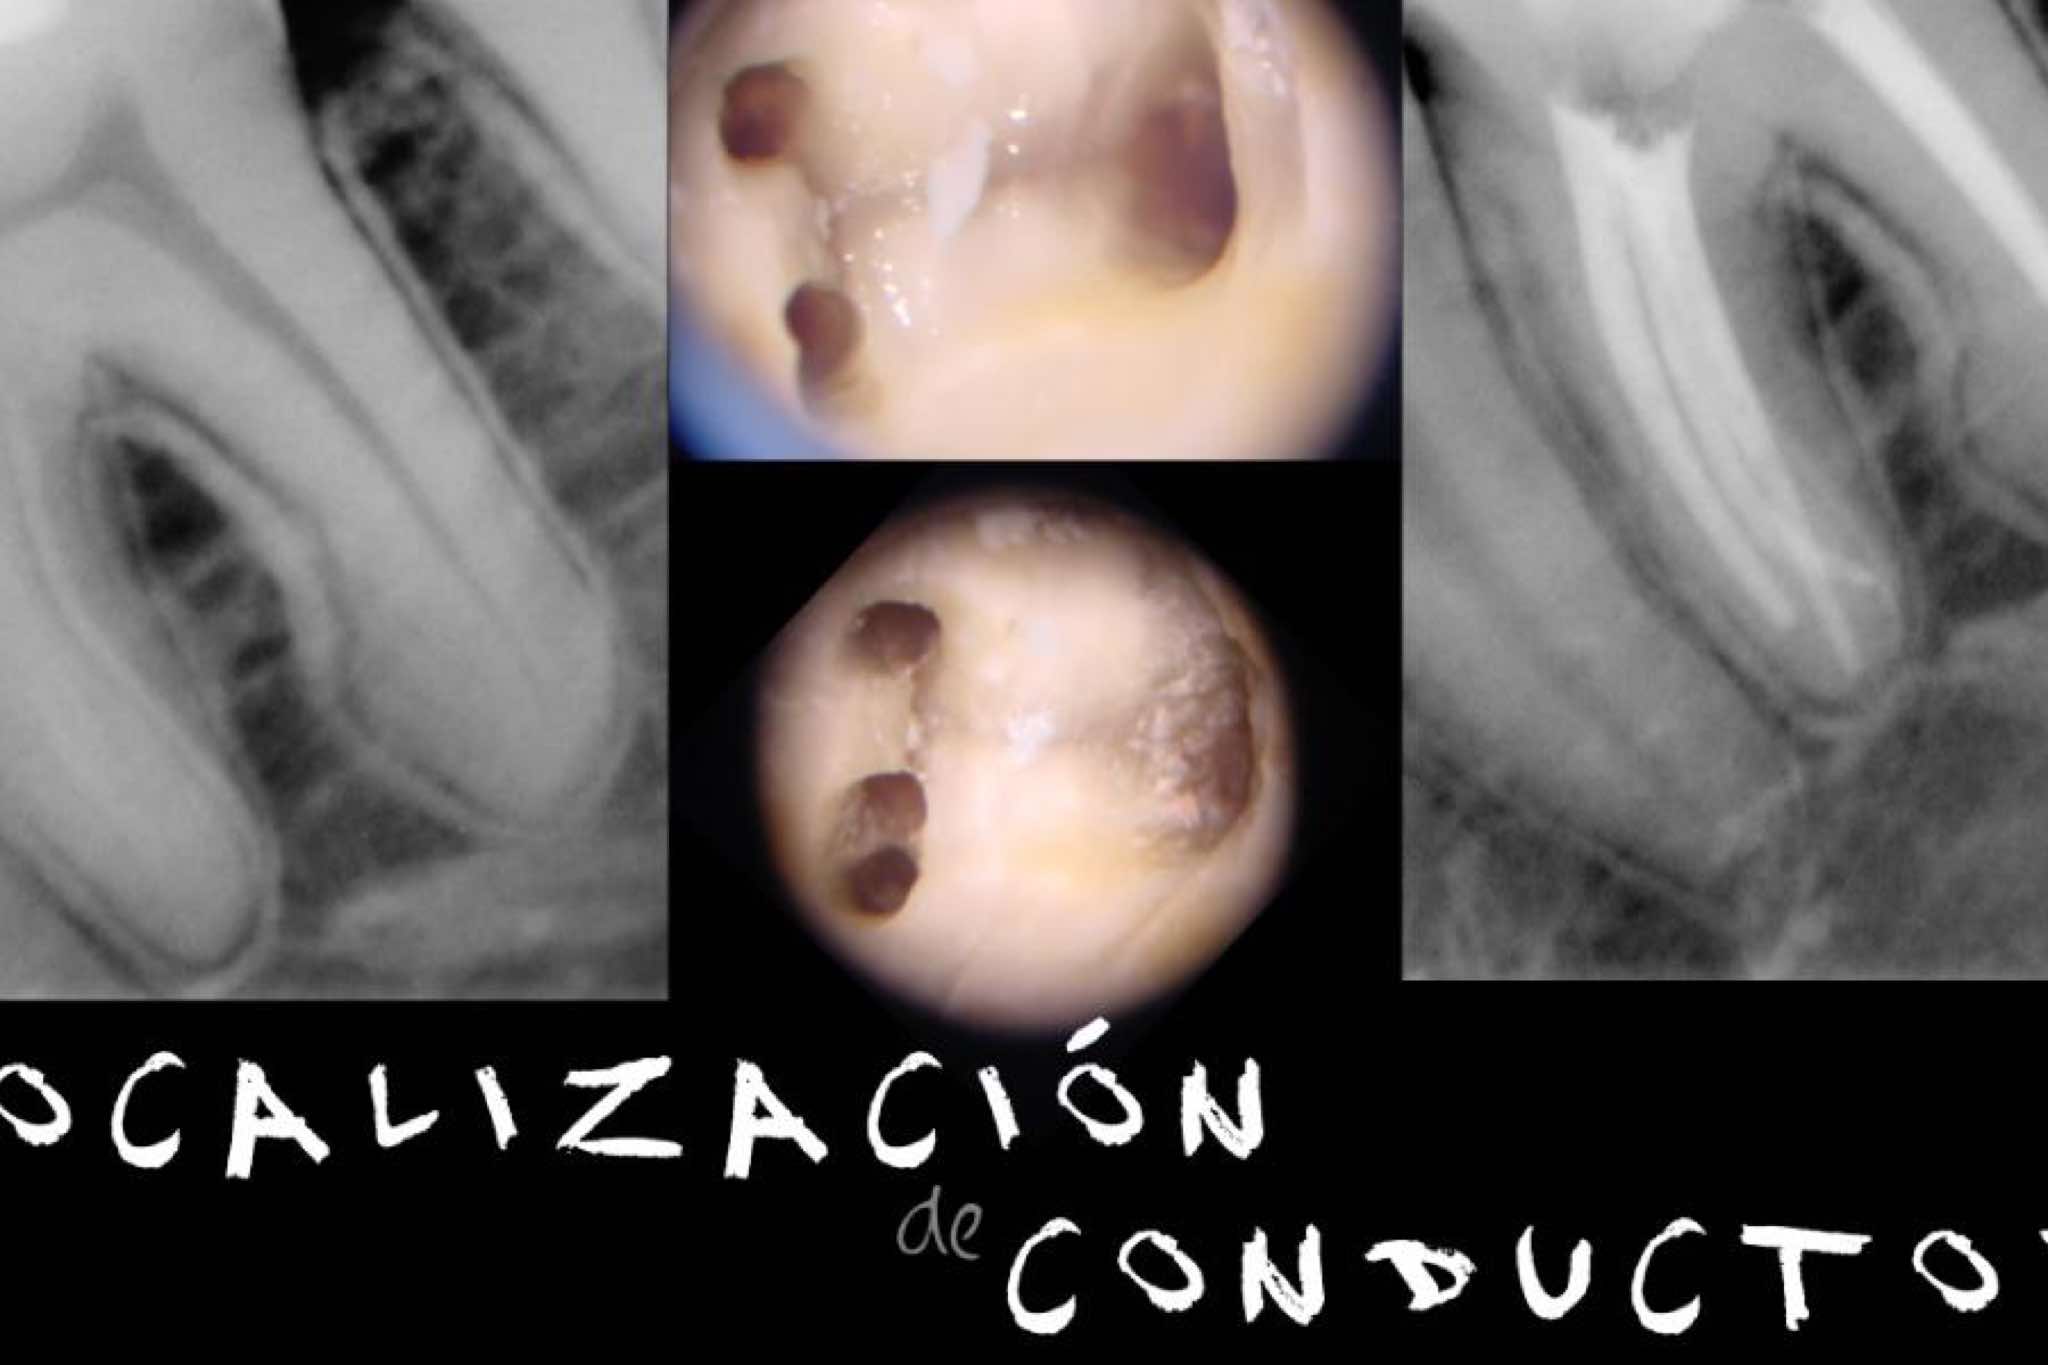

exibid_renocioninstrume2exibid_localizaciondeco2exibid_evasioninstrumen2exibid_retirodeposteyco2.jpegexibid_fracturavertical2exibid_retratamietoycir2